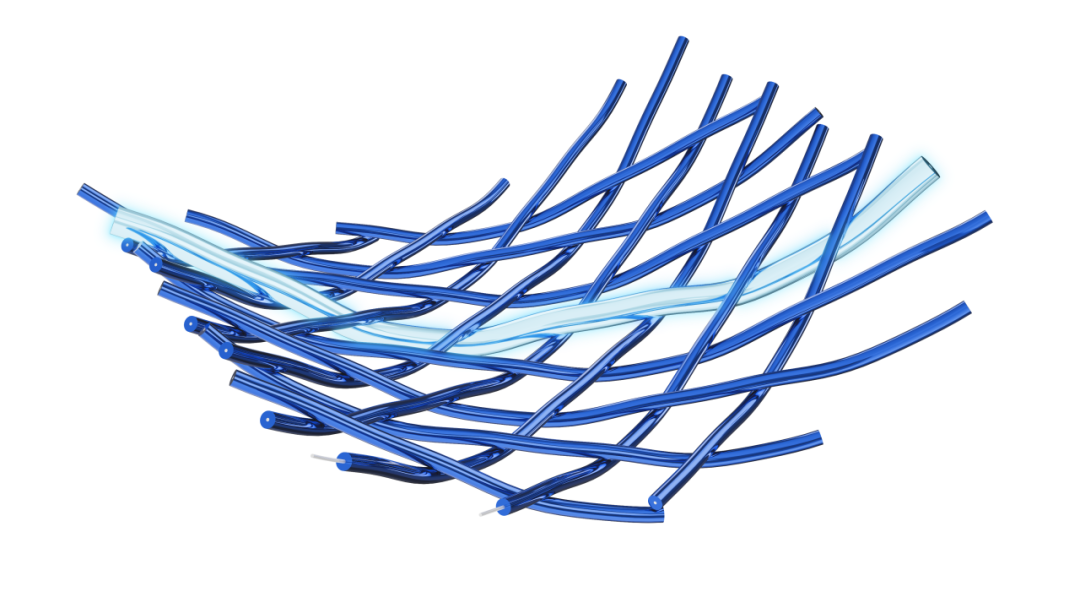

Tubridge Plus是“两维3D”、全程显影的密网支架。采用含铂芯的镍钛复合材料DFT丝编织而成,支架的每根编织丝都全程显影,同时两根双螺旋显影丝强化了支架局部贴壁效果,极大提升了颅底部位的可视性、更好地判断支架打开和贴壁的情况。

两维3D,全新升级

Tubridge Plus显影性能飞跃